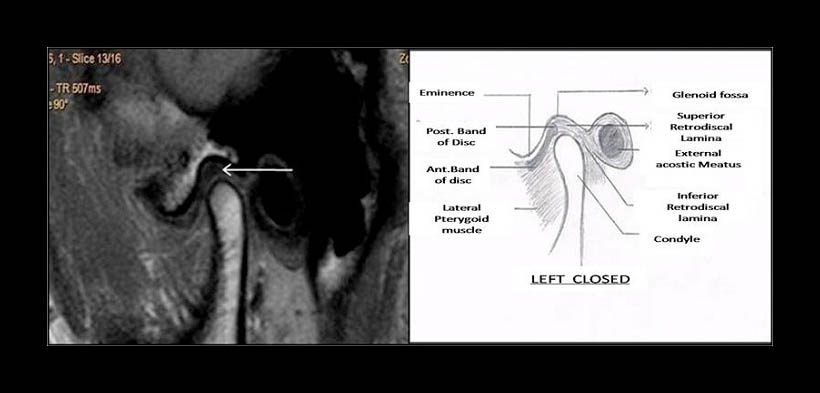

Fig. 3. DESPLAZAMIENTO DISCAL ANTERIOR EN BOCA CERRADA. Resonancia magnética de un paciente en boca cerrada. Se muestra desplazamiento anterior del disco articular con respecto al cóndilo mandibular y la cavidad glenoidea del hueso temporal.

Fig. 5. DESPLAZAMIENTO DISCAL ANTERIOR EN BOCA CERRADA. Resonancia magnética de un paciente en boca cerrada. Se muestra desplazamiento anterior del disco articular con respecto al cóndilo mandibular y la cavidad glenoidea del hueso temporal.